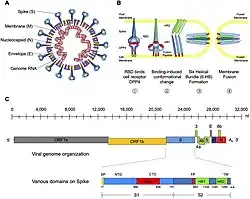

Middle East respiratory syndrome–related coronavirus (MERS-CoV),[1] or EMC/2012 (HCoV-EMC/2012), is the virus that causes Middle East respiratory syndrome (MERS).[2][3] It is a species of coronavirus which infects humans, bats, and camels.[4] The infecting virus is an enveloped, positive-sense, single-stranded RNA virus which enters its host cell by binding to the DPP4 receptor.[5] The species is a member of the genus Betacoronavirus and subgenus Merbecovirus.[6][4]

Due to the clinical similarity between MERS-CoV and SARS-CoV, it was proposed that they may use the same cellular receptor; the exopeptidase, angiotensin converting enzyme 2 (ACE2).[21] However, it was later discovered that neutralization of ACE2 by recombinant antibodies does not prevent MERS-CoV infection.[22] Further research identified dipeptidyl peptidase 4 (DPP4; also known as CD26) as a functional cellular receptor for MERS-CoV.[20] Unlike other known coronavirus receptors, the enzymatic activity of DPP4 is not required for infection. As would be expected, the amino acid sequence of DPP4 is highly conserved across species and is expressed in the human bronchial epithelium and kidneys.[20][23] Bat DPP4 genes appear to have been subject to a high degree of adaptive evolution as a response to coronavirus infections, so the lineage leading to MERS-CoV may have circulated in bat populations for a long period of time before being transmitted to people.[24]